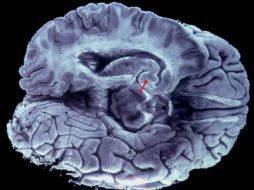

Tecnología Hallan mecanismo clave en la formación de tumores cerebrales 30 de abril de 2016 - 18:24 hs Estudios científicos Ciencia médica